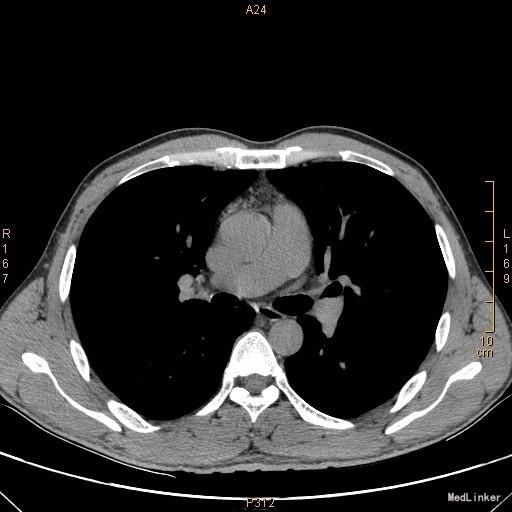

主诉:左眼睑下垂1年,加重半年。病史:患者1年前无明显诱因出现左眼睑下垂,抬起困难,伴视物重影,无言语不能、吞咽困难,无发热、头痛、恶心、呕吐、头晕、视物旋转、肢体麻木、饮水呛咳、视物模糊、肢体不自主运动、肢体抽搐、意识障碍、大小便失禁,休息后缓解,未予重视,半年来上述症状反复加重,10余天前至当地医院就诊,查新斯的明试验阳性,遂至我院神经内科就诊,胸部CT示:1、右肺尖钙化结节;2、胸腺增生。为了进一步治疗门诊拟“重症肌无力”收住我科。患者自起病以来,无发热、咳嗽、尿频、尿急、腹泻,无心悸、胸闷等,精神、食欲、睡眠好,体重无明显变化。

查体:左侧眼睑下垂,右侧眼裂宽10mm,左侧眼裂宽5mm。肺部查体未见异常。 辅查:新斯的明试验阳性。胸部CT示1、右肺尖钙化结节;2、胸腺增生。

该患者诊断“1.重症肌无力,眼肌型;2.右上肺钙化结节”明确,重症肌无力合并胸腺增生或胸腺瘤,有手术指征,我们为患者行胸腔镜下胸腺扩大切除术+右肺上叶楔形切除术。术后病理示:右上肺结节呈干酪样坏死,考虑结核。胸腺及纵隔脂肪均见淋巴增生。术后效果明显,患者左侧眼睑下垂较前好转,右侧眼裂宽10mm,左侧眼裂宽8mm,视物重影症状消失。